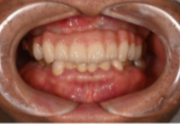

インプラントの症例紹介②

Before

After

主訴

歯がグラグラして噛めない

治療内容

上顎に対するインプラント治療を行った。

治療費

2,046,000円(税込)

治療期間

1か月

通院回数

3回

※治療回数は1回

想定されたリスク

※最終的な歯が入るまでは仮歯となりました。

One Dayインプラントなら、当日に仮歯が入り、すぐに噛めます。入れ歯の必要がなく、治療期間中も快適に過ごせる新しい選択肢です。